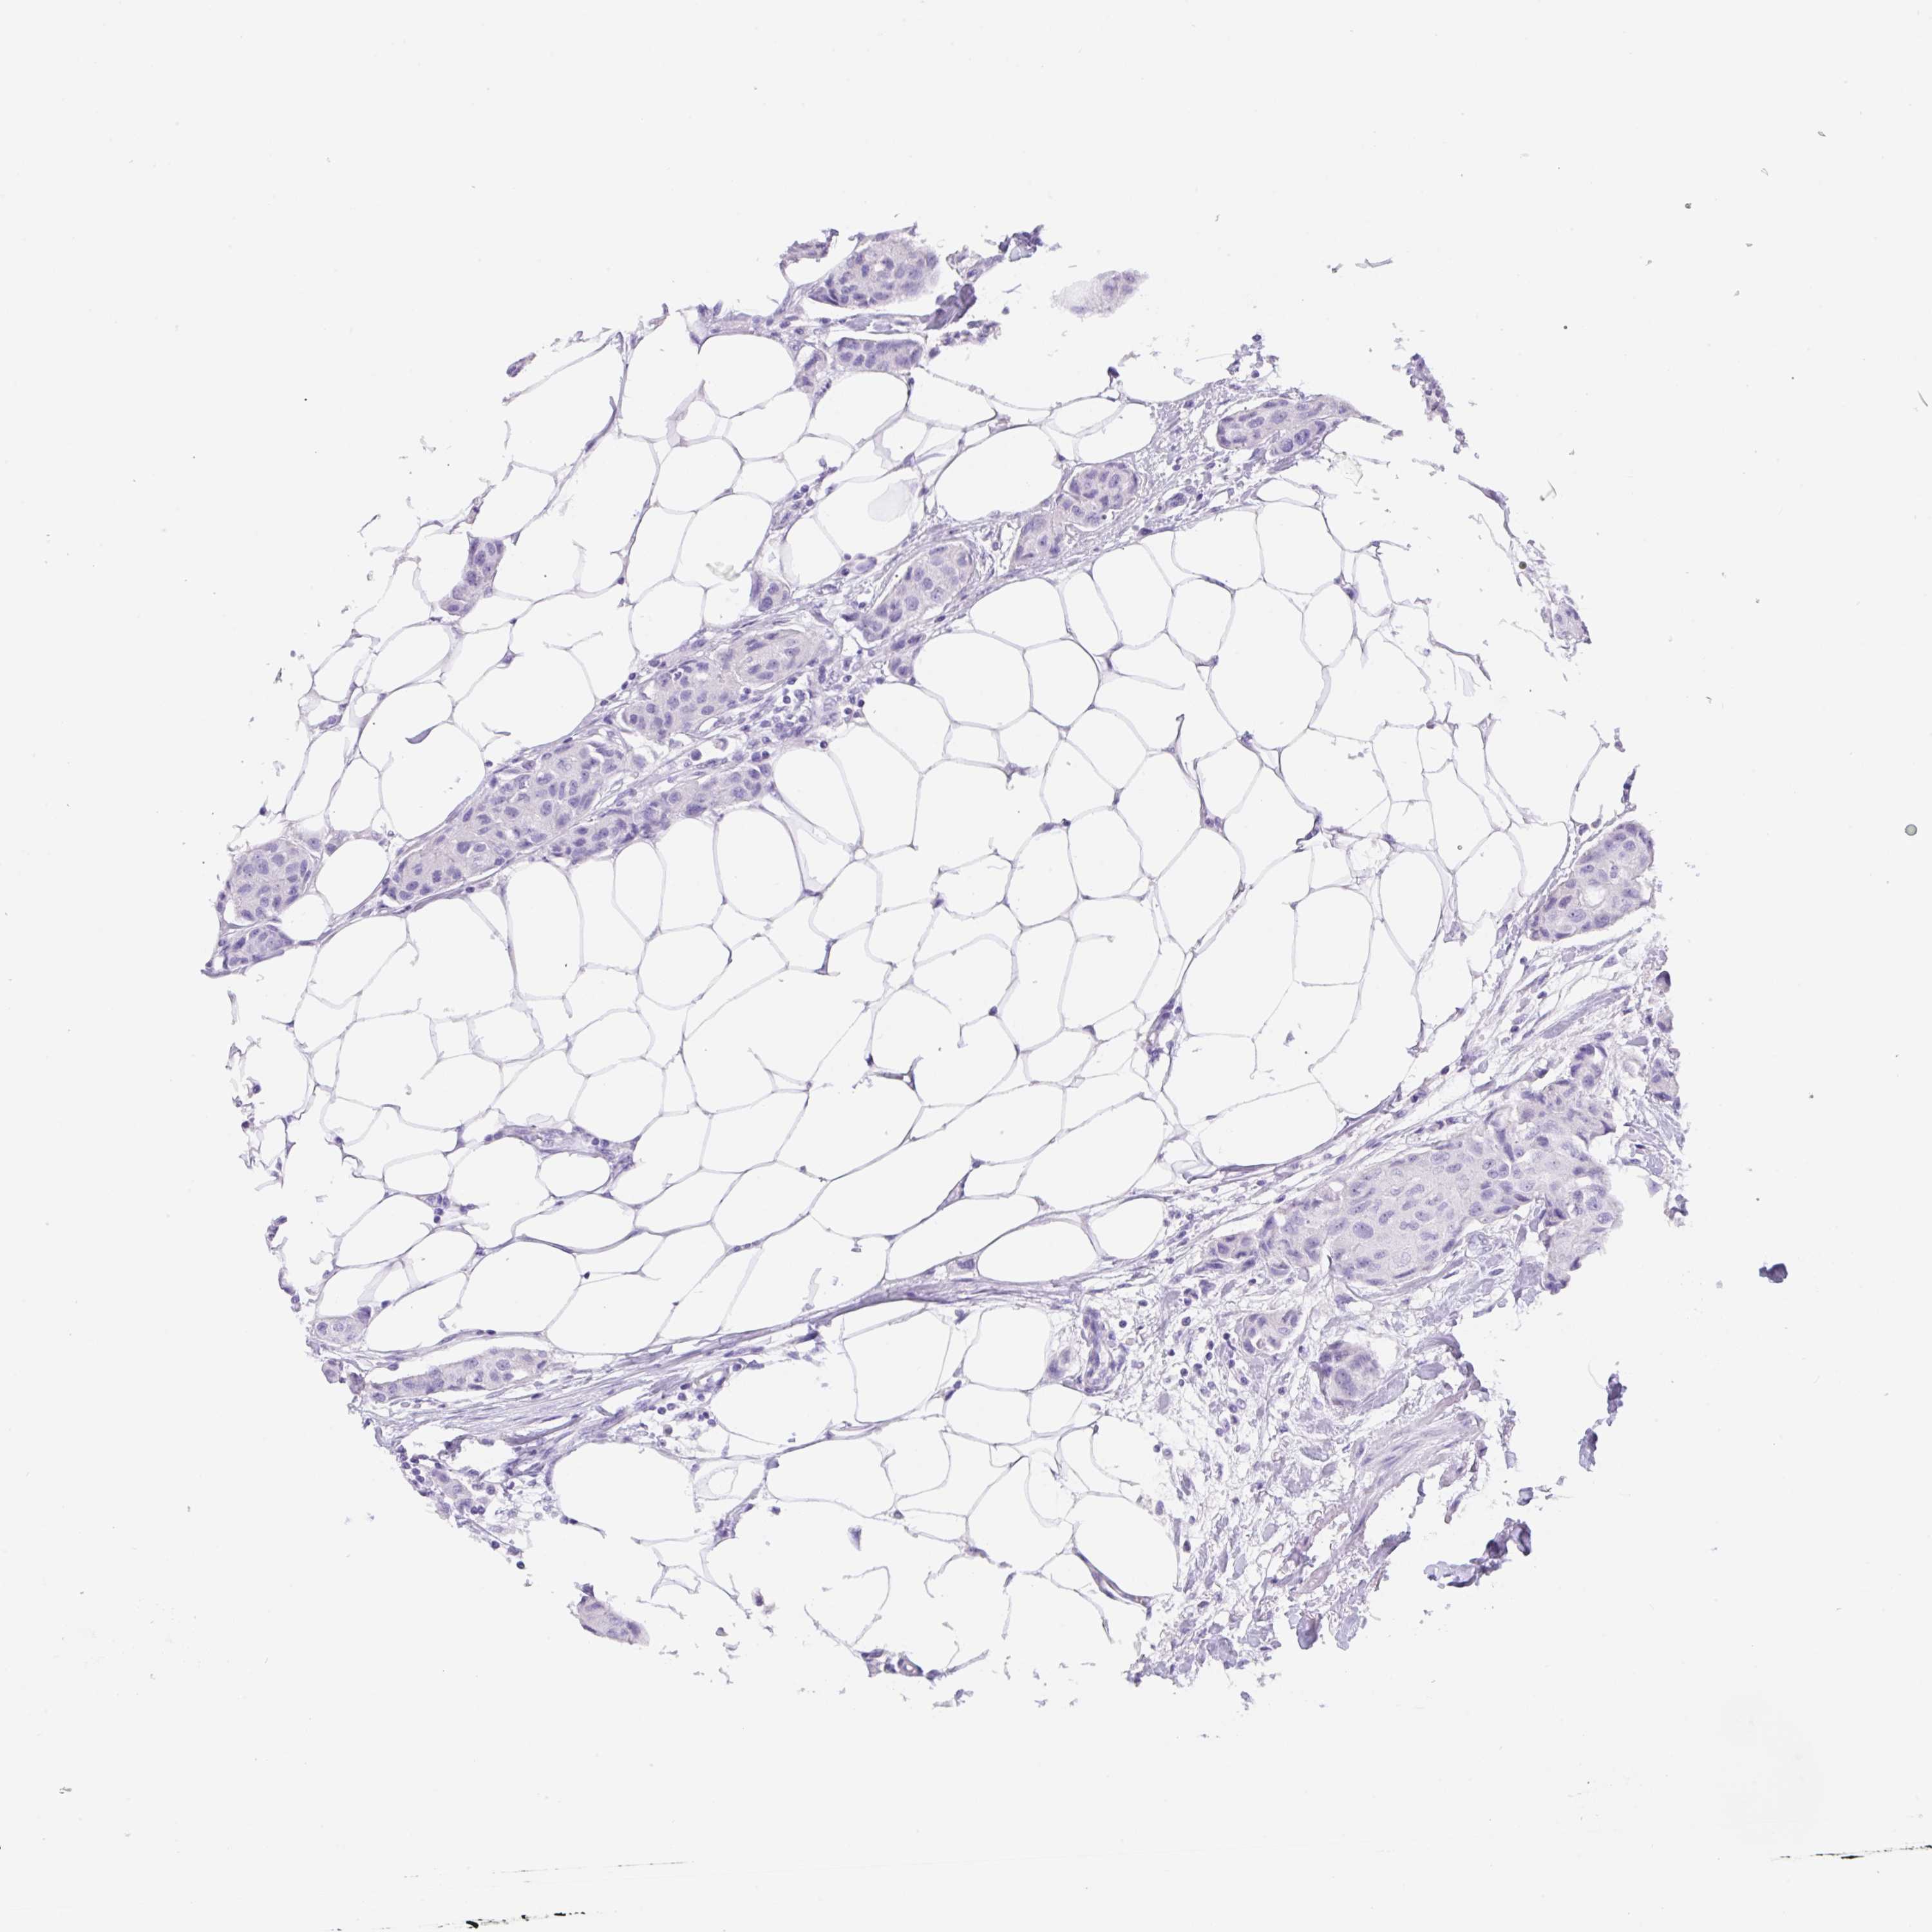

CANCER BREAST CANCER Show tissue menu

Breast cancer

Human cancer